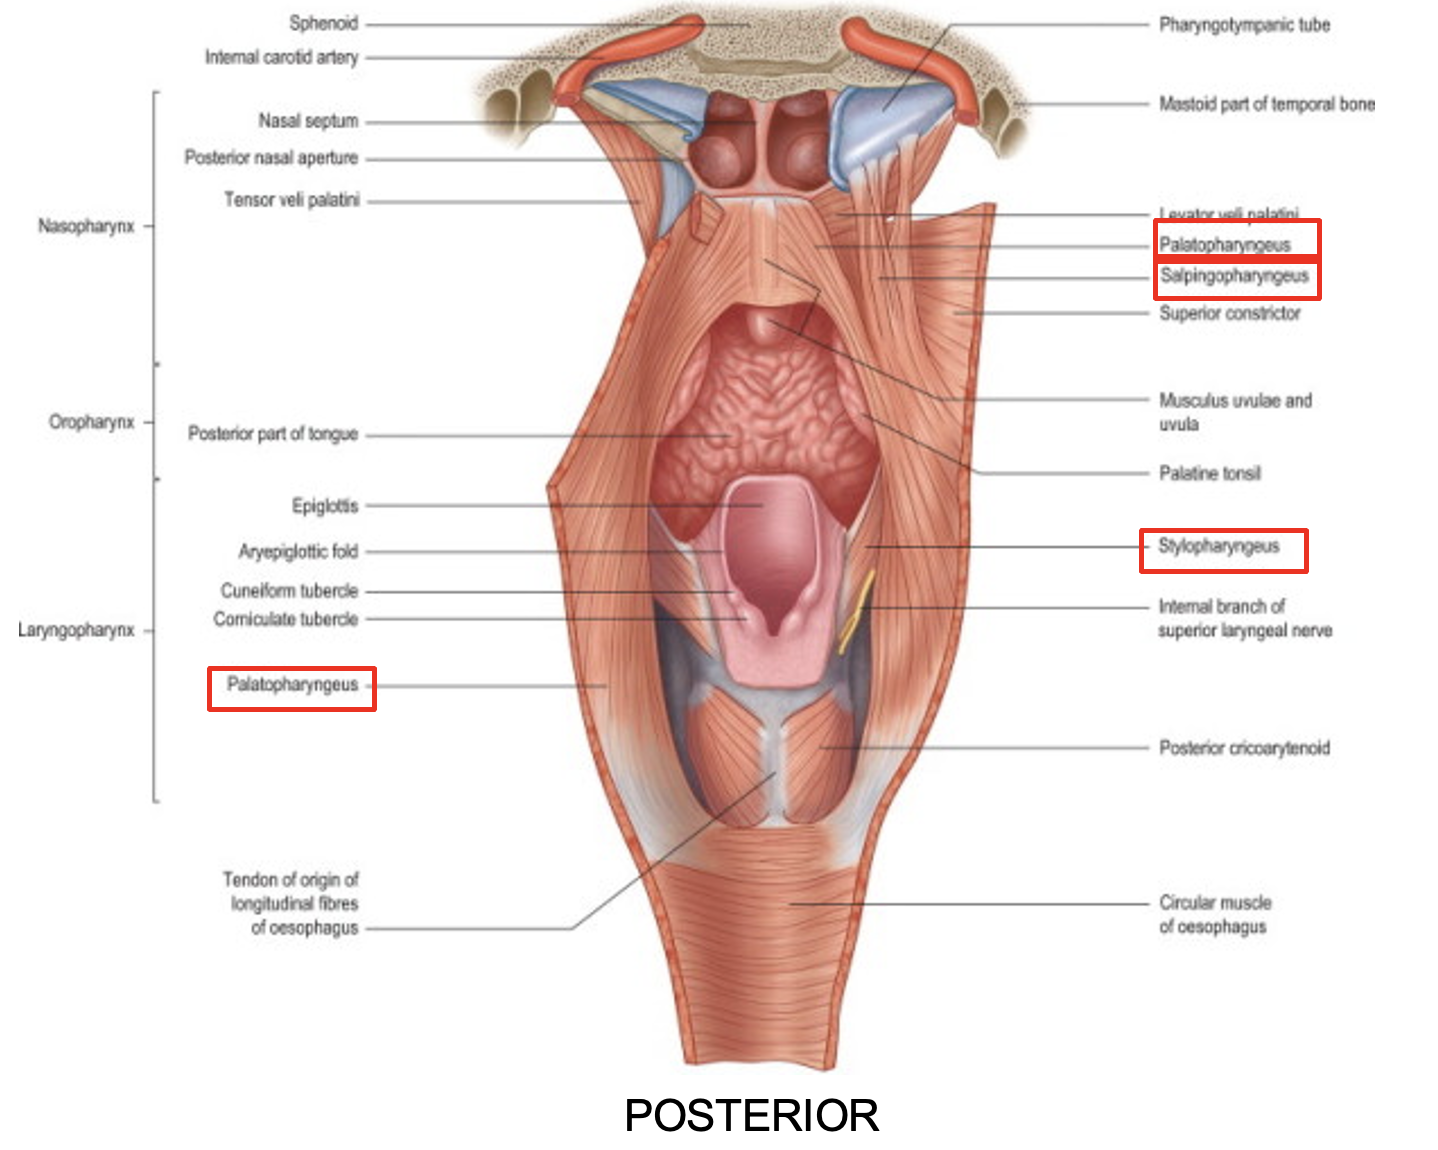

name the pharyngeal longitudinal muscles

three pairs of pharyngeal longitudinal muscles

stylopharyngeus

salpingopharyngeus

palatopharyngeus

function of the pharyngeal longitudinal muscles